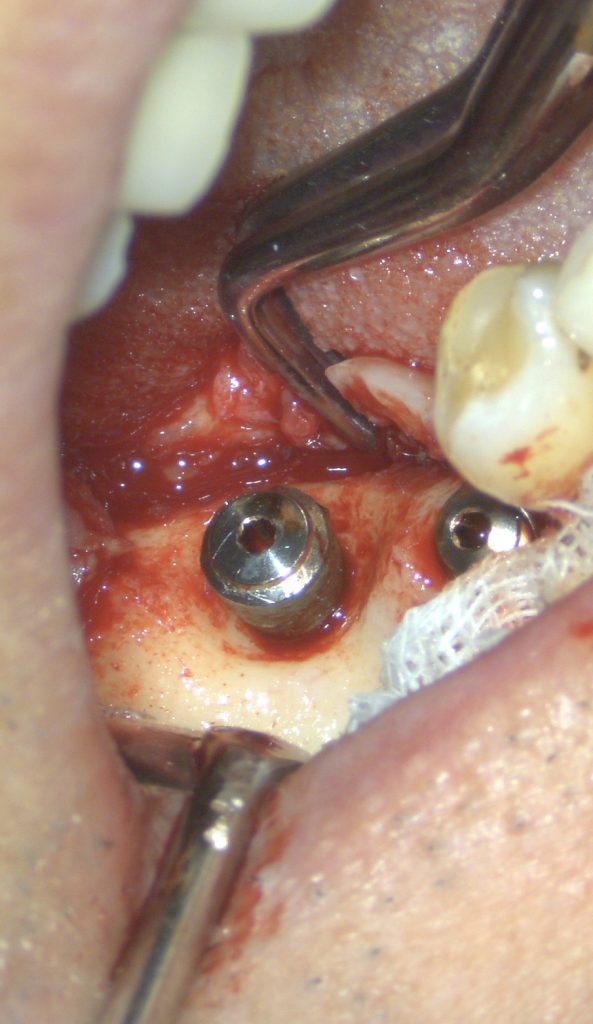

手術時と術後4ヶ月の写真です。

4ヶ月前のオペ時のビデオです。